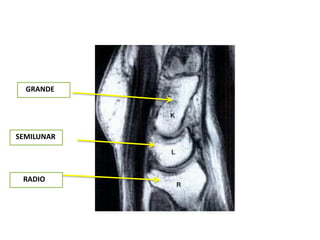

GRANDE

SEMILUNAR

RADIO